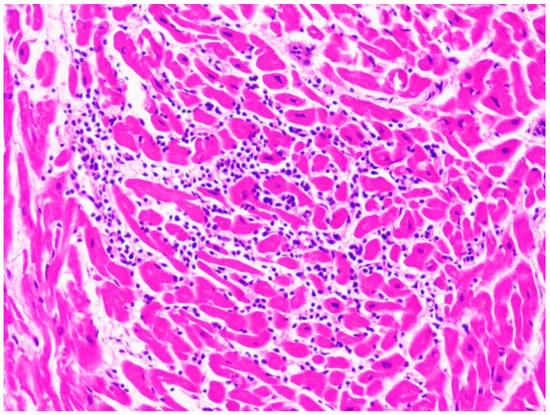

Dilated Cardiomyopathy (DCM) has a prevalence of 1/2500 [79]. Its mortality rate is up to 20% [80]. Death is usually due to heart failure or ventricular arrhythmias. SCD has an incidence of about 2–3%, can be the first manifestation of disease and is caused by electromechanical dissociation or arrhythmias [81]. LV dilatation and contractile impairment are the main risk factors for sudden death [82]. Greater left atrial volume also increases the risk of adverse outcomes [83]. In the paediatric population, the predictors of SD are the age at diagnosis, familiarity, and severe LV systolic disfunction [81]. At the forensic autopsies, DCM is macroscopically characterised by the dilatation of the cardiac chambers (greater in the ventricles than in the atria). These signs can be associated with other common findings, like intracavitary thrombi and, in case of right heart failure, hepatomegaly, ascites and peripheral oedema [79]. At the histopathologic examination, diffuse fibrosis with some areas of necrosis and atrophied and/or hypertrophied cardiomyocytes is usually found (Figure 5). Fibrosis plays an important role in this disease since it causes contractile impairment and ventricular re-entrant arrhythmias [84]. In DCM, two kinds of fibrosis can be found: interstitial and replacement fibrosis. Fibrosis results from the so-called “replacement”, which consists of myocyte cell death and scarring formation or directly from an expansion of interstitial collagen [85]. Replacement fibrosis is of great clinical significance because it is associated with sustained or inducible VT [86]. On the other hand, interstitial fibrosis, that is almost always found in DCM cases, is thought to cause focal tachycardias and to be involved in the maintenance of re-entry circuits [87].

DCM has many possible causes. It is usually distinguished in primary (congenital) and secondary (acquired). Secondary DCM can be caused by many factors, like toxic substances (e.g., cocaine or a chronic alcohol intake > 80 g/day), pathogens (virus, bacteria, fungi, spirochete, protozoans, rickettsia), endocrine or metabolic disfunctions (electrolyte disturbances, Cushing’s disease), inflammatory conditions, and autoimmune or neuromuscular diseases [81]. It is important to note that DCM can be also a long-term toxic manifestation: for example, it can occur even 10 years after chronic anthracycline exposure [81]. Therefore, when DCM is found at the autopsy, the main tool for differential diagnosis is a complete and accurate anamnesis. From a macroscopic point of view, at the autopsy it can be difficult to differentiate DCM from ischemic cardiomyopathy, hypertensive heart disease, athlete’s heart, and other cardiomyopathies [82]. In particular, the presence of significant coronary stenosis allows to distinguish ischemic cardiomyopathy from DCM. Instead, the differential diagnosis between DCM and left ventricular noncompaction is performed through the identification of LV trabeculations, deep intertrabecular recesses, and a thin layer of normal myocardium. Histopathological examination can be of great help to distinguish a DCM from a viral or immune-mediated myocarditis thanks to the identification of a lymphocytic infiltrate (Figure 6) and, in case of infective myocarditis, the post-mortem microbiological testing (PCR) [81].

Figure 5. Mild fibrosis and increased nuclear-cytoplasmic ratio in the cardiomyocytes of the heart of a 45-year-old woman affected by dilated cardiomyopathy (hematoxylin and eosin stain, 40× magnification).

Figure 6. Lymphocytic infiltrate in the case of a 10-year-old child affected by myocarditis (hematoxylin and eosin stain, 40× magnification).